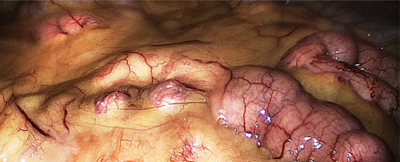

See this toxic fat?

If you’re an overweight or obese woman, you’ve got plenty of that . . . and it produces estrogen, and that ain’t good!